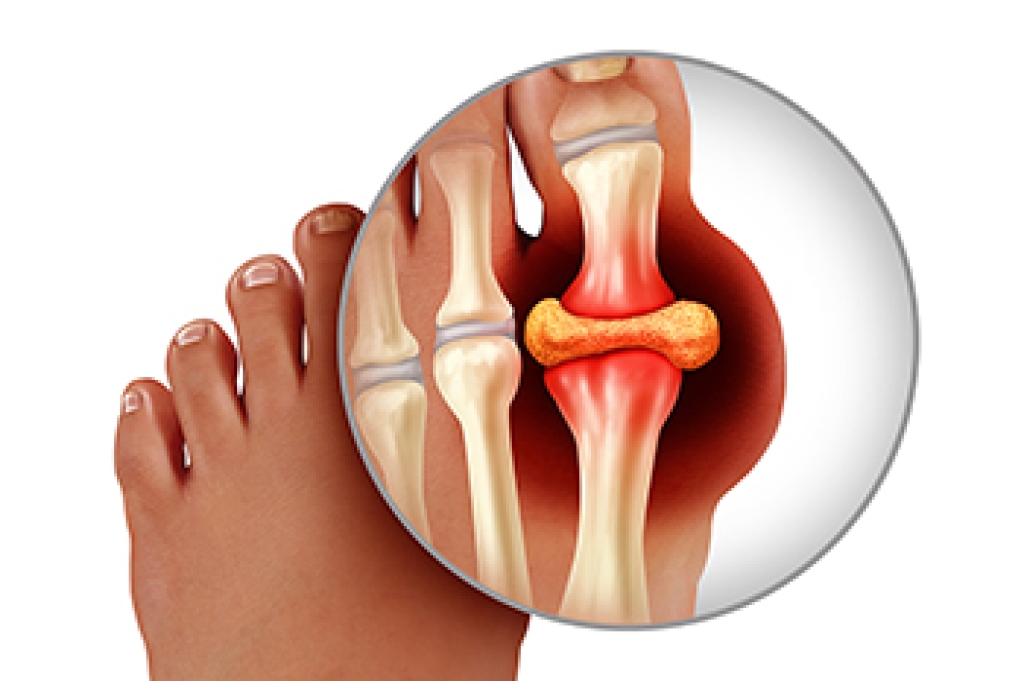

Gout is a painful form of inflammatory arthritis that occurs when uric acid crystals build up in a joint, most often the big toe. This condition can develop due to high uric acid levels, certain foods, dehydration, or underlying medical issues. Risk factors include family history, obesity, kidney disease, and diets high in red meat or alcohol. Symptoms often include sudden sharp pain, redness, swelling, and warmth in the affected joint. A podiatrist can diagnose gout, provide relief through targeted treatment, and recommend lifestyle changes to reduce flare ups. If your big toe and surrounding areas are causing you pain, it is suggested that you promptly consult a podiatrist who can accurately diagnose gout, and help you to manage this painful condition.

Gout is a form of arthritis that is characterized by sudden, severe attacks of pain, redness, and tenderness in the joints. The condition usually affects the joint at the base of the big toe. A gout attack can occur at any random time, such as the middle of the night while you are asleep.

- Intense Joint Pain - Usually around the large joint of your big toe, and it most severe within the first four to twelve hours

- Inflammation and Redness -Affected joints may become swollen, tender, warm and red